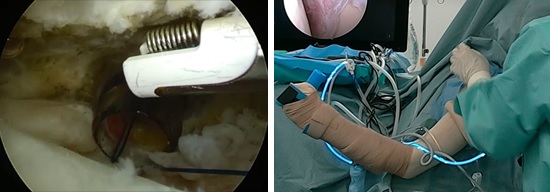

鏡視下滑膜切除(クリーニング手術)

肩関節鏡視下に痛みの原因となっている充血した滑膜を可及的に切除します。